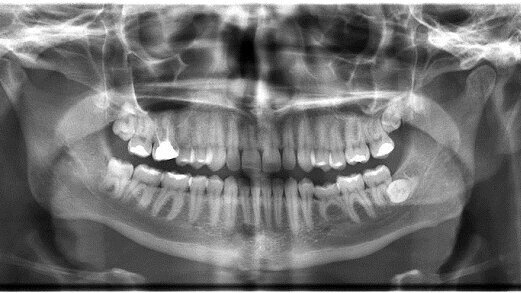

GÖTEBORG - Een röntgenopname van de kaak kan voorspellen of een patiënt een verhoogd risico loopt op fracturen in de rest van het lichaam. Dit melden onderzoekers van de Universiteit van Göteborg in Nature Reviews Endocrinology.

In een eerdere studie hebben onderzoekers van dezelfde universiteit bewezen dat bij een dunne botstructuur in het trabeculaire bot in de onderkaak er een grotere kans is op breuken in andere delen van het lichaam. Zij hebben nu aangetoond dat tandheelkundige röntgenfoto’s de botstructuur in de onderkaak laten zien, zodat voorspeld kan worden wie een verhoogd risico op fracturen loopt.

“Röntgenopnamen van de kaak bevatten veel informatie over de botstructuur,” zegt onderzoeker Grethe Jonasson. “Door het analyseren van deze beelden kunnen tandartsen mensen met een verhoogd risico op fracturen identificeren, lang voordat de eerste fractuur zich voordoet.”

De studie is gebaseerd op gegevens uit een bevolkingsonderzoek onder vrouwen in Göteborg. Sinds 1968 werden 731 vrouwen tussen 38 en 60 jaar meerdere malen onderzocht. Beelden van hun kaakbot werden geanalyseerd en vergeleken met de incidentie van latere fracturen.

De botstructuur van de kaak was dun bij ongeveer 20% van de vrouwen in de leeftijd van 38 tot 54. Op latere leeftijd liepen deze vrouwen een significant hoger risico op fracturen. Naarmate mensen ouder worden, is het verband tussen de botstructuur in de kaak en breuken in andere delen van het lichaam sterker. Hoewel de studie werd uitgevoerd bij vrouwen, denken de onderzoekers dat het verband ook geldt voor mannen. (bron: Tandartspraktijk)